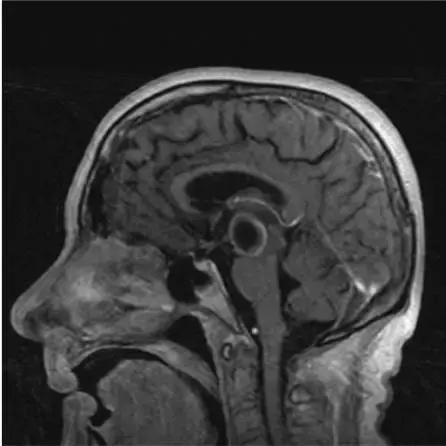

松果体囊肿